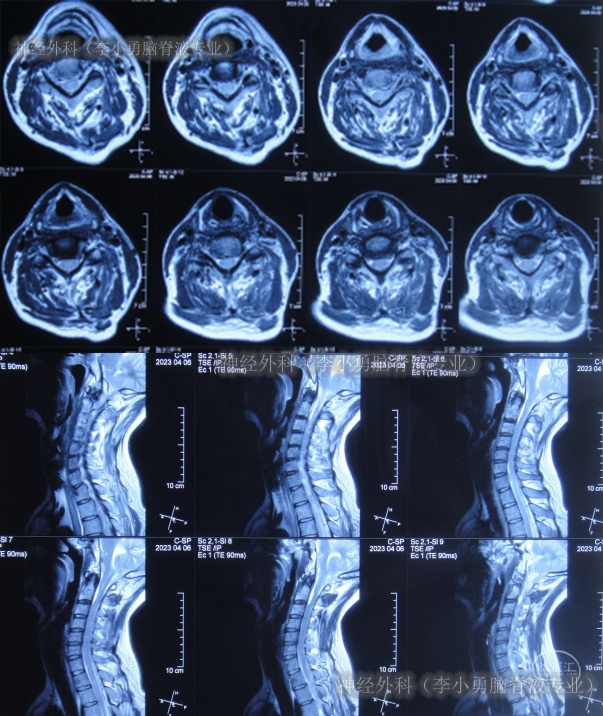

住院治疗54天即2023年4月6日,查颈髓核磁(图-26)后继续给予对症治疗。

图-26:2023年4月6日颈髓核磁